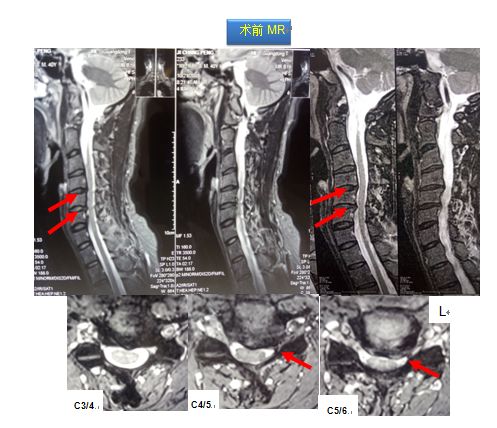

考虑诊断:1.脊髓型颈椎病(C3-6椎间盘突出并相应椎管狭窄) 2.颈背胸部肌筋膜综合征

其后按计划实施我院特色术式:改良精准微创式颈椎椎板成形术(该技术是在梁徳主任指导下由江晓兵副教授改良),手术按照标准化流程下进行,术中耗时60分钟,出血量约50 ml。术后复查如下:

术后MRI可见椎管内空间增大,脊髓后移退让,脊髓周围受压完全解除,术后患者双下肢乏力症状彻底消失。